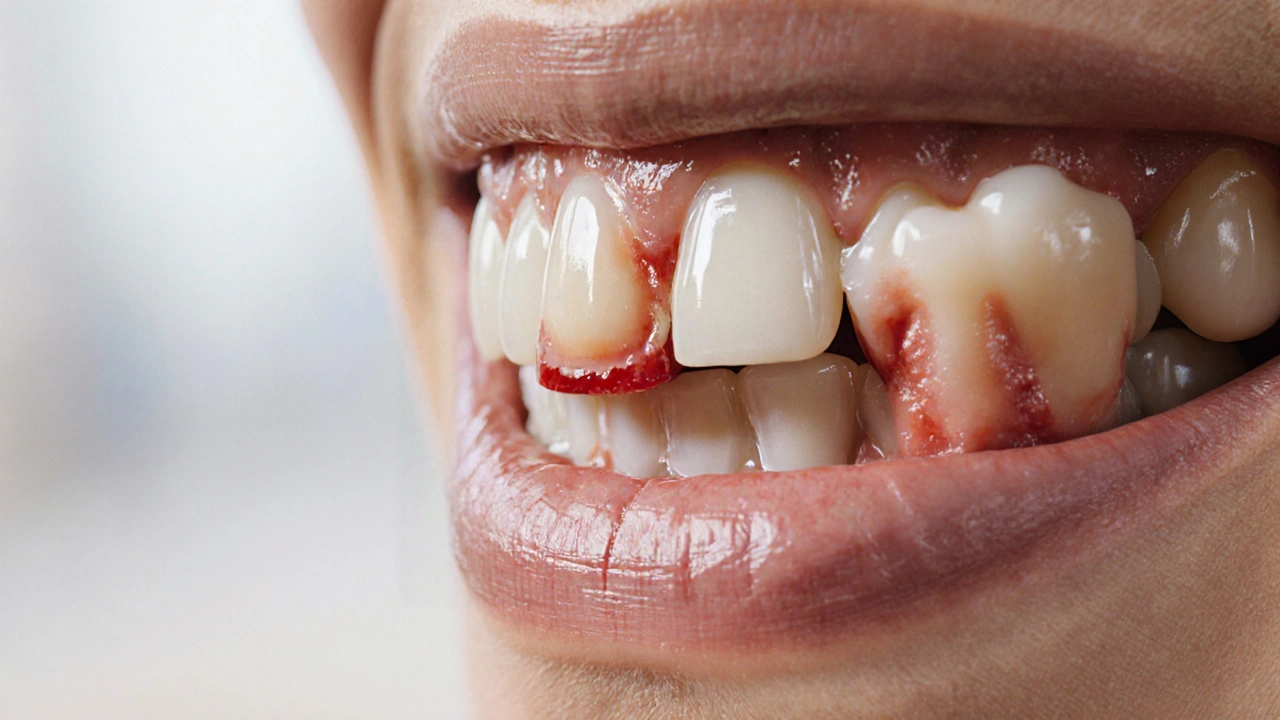

- Zánět dásní - částečně vystupující zub může způsobit lokální zánět (zánět dásní), což vyvolává otok a bolest.

- Otok dásní nad nebo pod zubem, často růžové až červené barvy.

zánět dásní | červená, citlivá dásně, zápach |